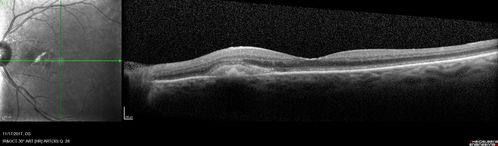

Pattern Dystrophy - Adult Vitellifrom (Best)

71 year old female - lesions nasal to the fovea in both eyes. (20/40 OU)

Adult Vitelliform Pattern Dystrophy - Nasal to Fovea